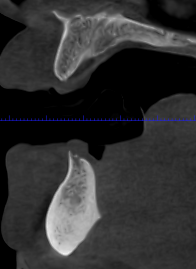

En este contexto, la tomografía computarizada de haz cónico (CBCT) se ha convertido en una herramienta esencial para los profesionales de la odontología. Gracias a la radiología 3D, los especialistas pueden evaluar con exactitud el volumen óseo disponible, identificar estructuras anatómicas importantes (como el nervio dentario o el seno maxilar) y diseñar el tratamiento con la máxima previsión y seguridad.

Para el paciente, esto se traduce en procedimientos más seguros, menos invasivos y con resultados más predecibles. En la fase de seguimiento, el CBCT también permite comprobar la correcta integración del injerto óseo y la evolución del tejido antes de colocar el implante definitivo.